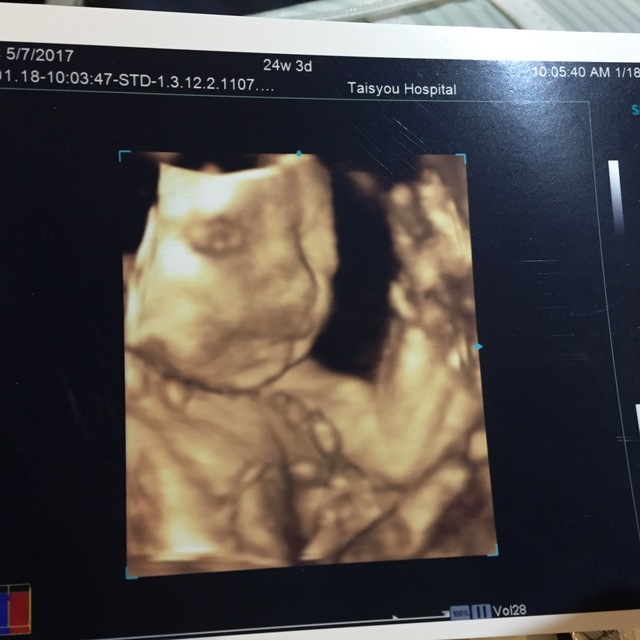

24週3日(24w3d・女の子)|keee_8 さん(23歳)

エコー写真撮影時のエピソード:

初めて顔がはっきりわかるエコー写真でした。こんなにもパパに似るものかと夫婦で笑い、お互いの家族に写真を撮る送りました。両親も自分たちの頃とは違ってよく顔がわかるね!と言っていました。

もちろん、パパに似てる!似すぎだ!!と大騒ぎです。旦那はうれしくて友だちにまで見せていました。